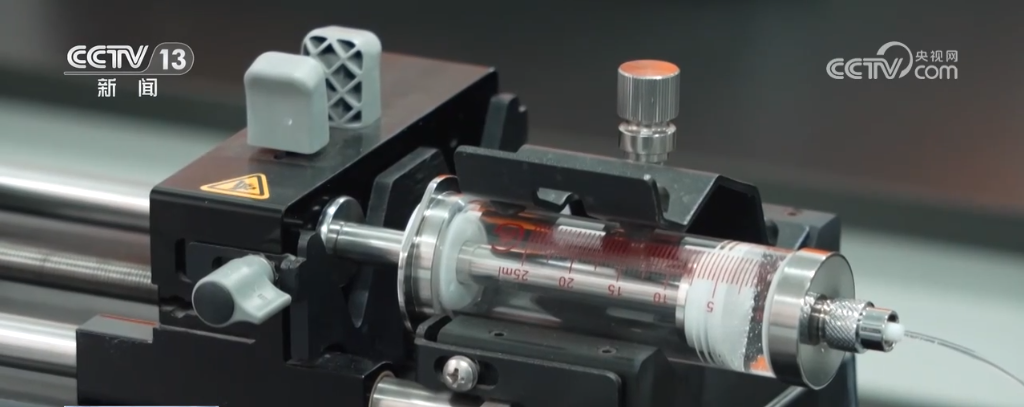

北大新突破:一滴血 查清病从哪来

最近,北京大学何爱彬团队联合多方合作者在国际权威期刊发表最新研究成果。 他们研发出具有自主知识产权的新一代表观液体活检技术cf-EpiTracing,实现仅靠少量血浆样本,就能精准识别病变来源组织、发现早期病2026-03-09 -